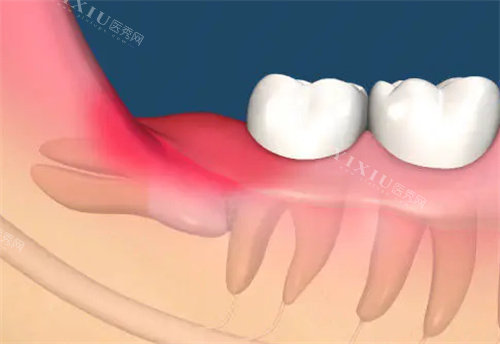

智齿,作为口腔中然后萌出的牙齿,常常因为位置不佳而引发各种问题。很多人的智齿生长空间不足,无法正常萌出,导致部分牙冠被牙龈覆盖,形成一个盲袋。食物残渣很容易嵌塞在这个盲袋里,难以清洁干净。时间一长,细菌就会在盲袋内大量繁殖,引发炎症,也就是我们常说的智齿冠周炎。此外,如果智齿本身存在龋坏,或者与邻牙之间形成了缝隙,也容易导致食物滞留和细菌滋生,进而引发反复发炎。